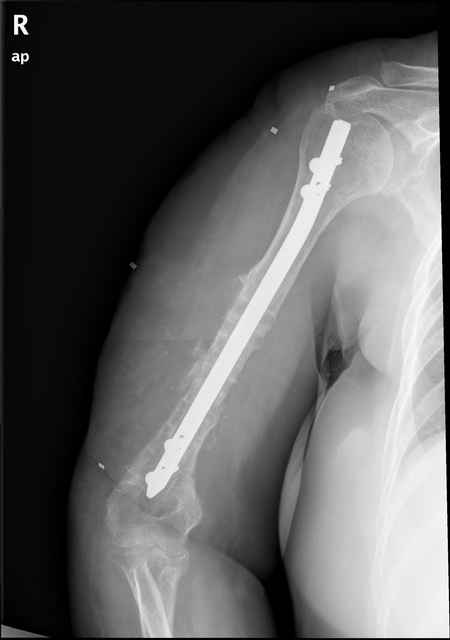

Больная 48 лет, медсестра-массажист, перелом плеча 7 лет назад, оперирована 4-кратно и безуспешно

Больная 48 лет, медсестра. Травма получена 7 лет назад, оперирована первично в Турции - остеосинтез пластиной - несращение - реостеосинтез стержнем там же через год (обычным, с выстоянеием его в полость плеча) - несращение - поступила к нам впервые в марте 2008 года - удаление стержня, реостеосинтез пластиной и костная пластика, в течение 2 лет лизис кости вокруг винтов, смещение фиксатора, в марте 2010 - удаление пластины, реостеосинтез интрамедуллярным стержнем с блокированием (рассверливание + костная пластика). В динамике - вновь лизис в области перелома, нестабильность дистальных блокирующих винтов.

Да, принципиально что-то такое тут подошло бы. Но тут дефект, и надо точно подсчитать, не длинноват ли стержень, а то, может, после плотного контакта он вылезет в локтевую ямку.

Клинически фиксация пока действительно стабильна, но на рентгенограммах резорбция кости в области дистальных блокирующих винтов и миграция одного из них.